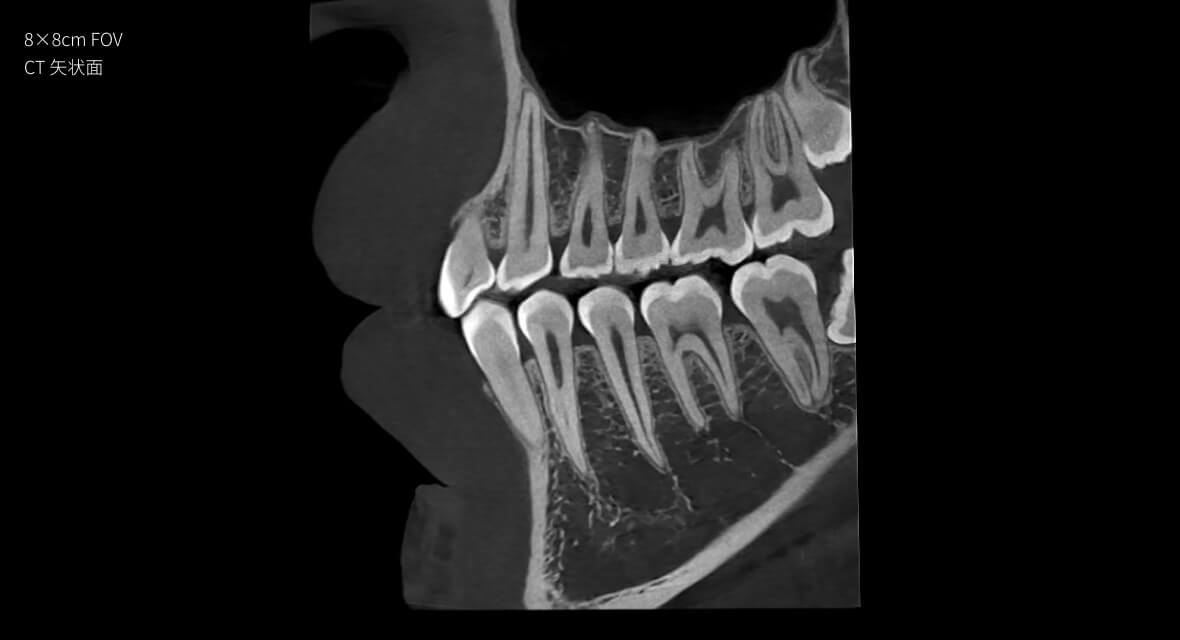

• 3D全景

數字全景

16×15cm

非拼接大視野

28lp/cm

高精準

只需一次單圈掃描即可獲得CT、數字全景和3D正/側位影像,

并能同時生成3D TMJ視圖 提高診療效率,避免過度檢查,減少患者所受的輻射